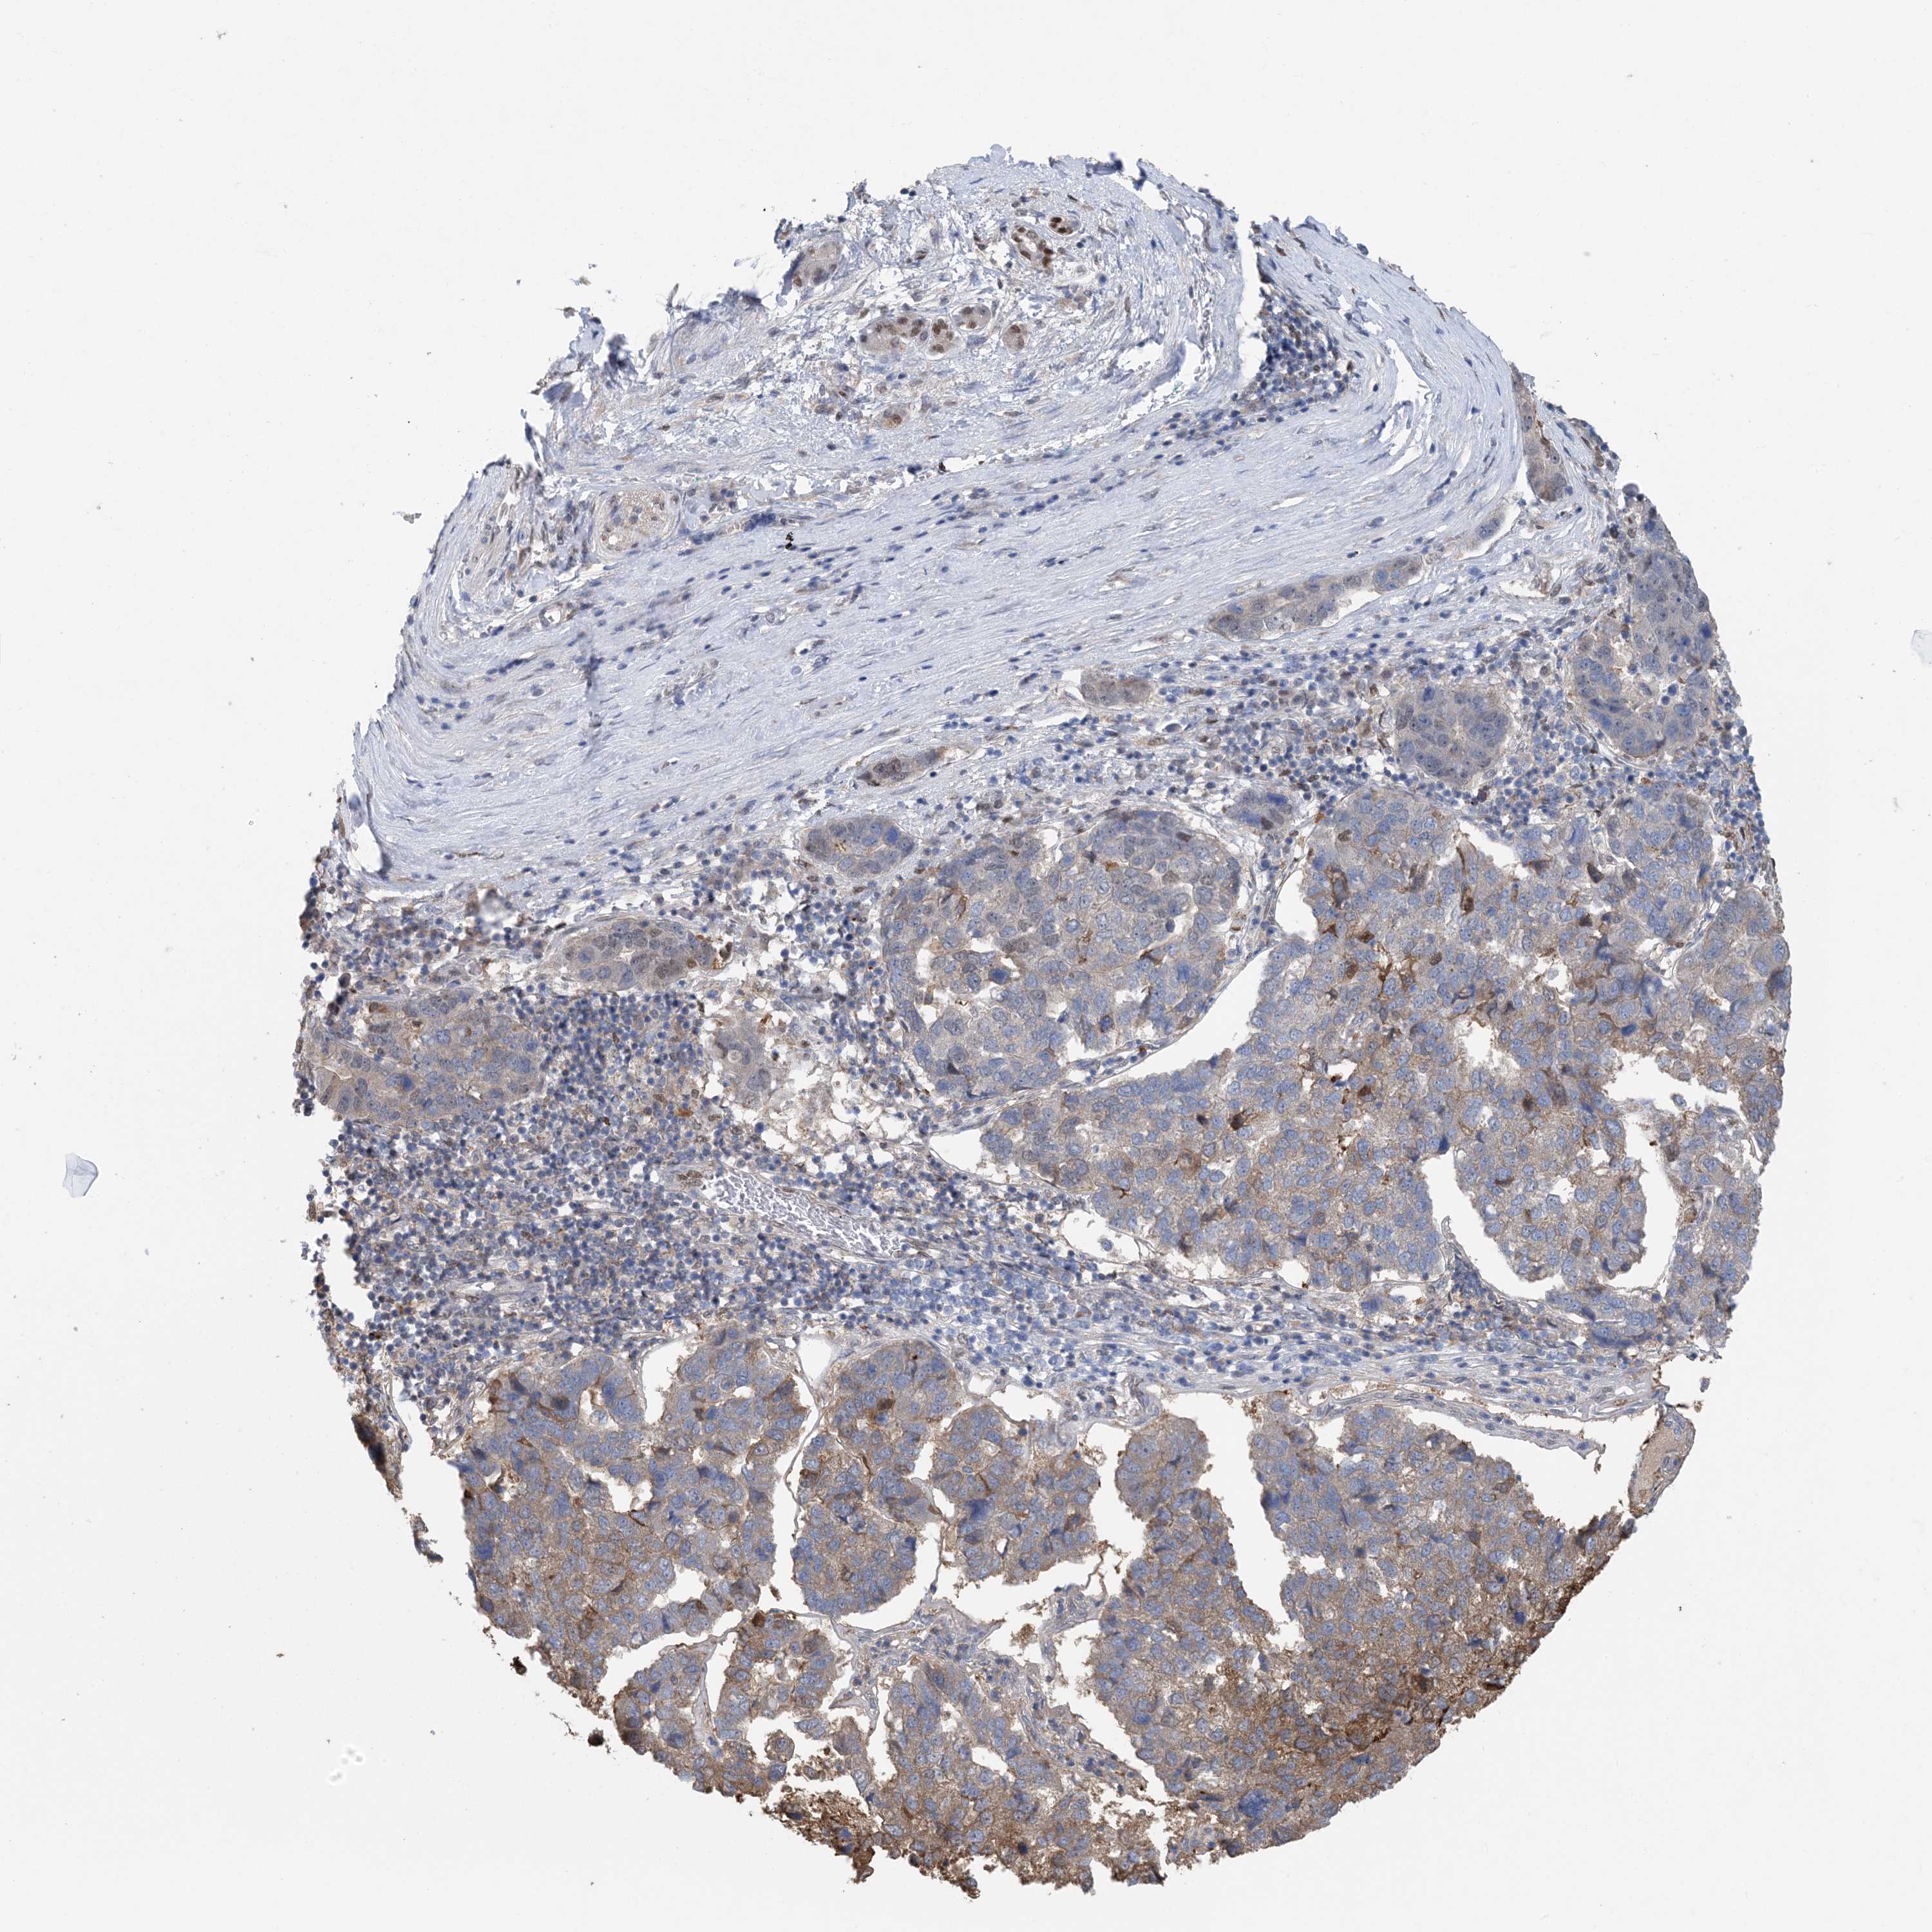

PANCREATIC CANCER - Protein expressioni

A mouse-over function shows sample information and annotation data. Click on an image to view it in a full screen mode. Samples can be filtered based on level of antibody staining by selecting one or several of the following categories: high, medium, low and not detected. The assay and annotation is described here.

Note that samples used for immunohistochemistry by the Human Protein Atlas do not correspond to samples in the TCGA dataset.

Antibody stainingi

Antibody staining in the annotated cell types in the current human tissue is reported as not detected, low, medium, or high, based on conventional immunohistochemistry profiling in selected tissues. This score is based on the combination of the staining intensity and fraction of stained cells.

Each image is clickable and will lead to virtual microscopy that enables deeper exploration of all samples and also displays staining intensity scores, fraction scores and subcellular localization as well as patient and tissue information for each sample.

Antibody HPA035063

Antibody HPA035064

Staining

High

Medium

Low

Not detected

Intensity

Strong

Moderate

Weak

Negative

Quantity

>75%

75%-25%

<25%

None

Location

Nuclear

Cytoplasmic/membranous

Cytoplasmic/membranous,nuclear

Adenocarcinoma, NOS